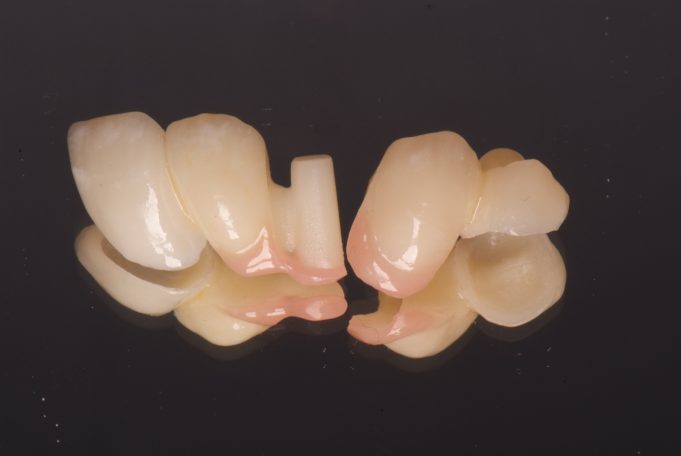

Vollkeramische Teilungsbrücke zum Ersatz der fehlenden Zähne und minimalinvasiver Verankerung.